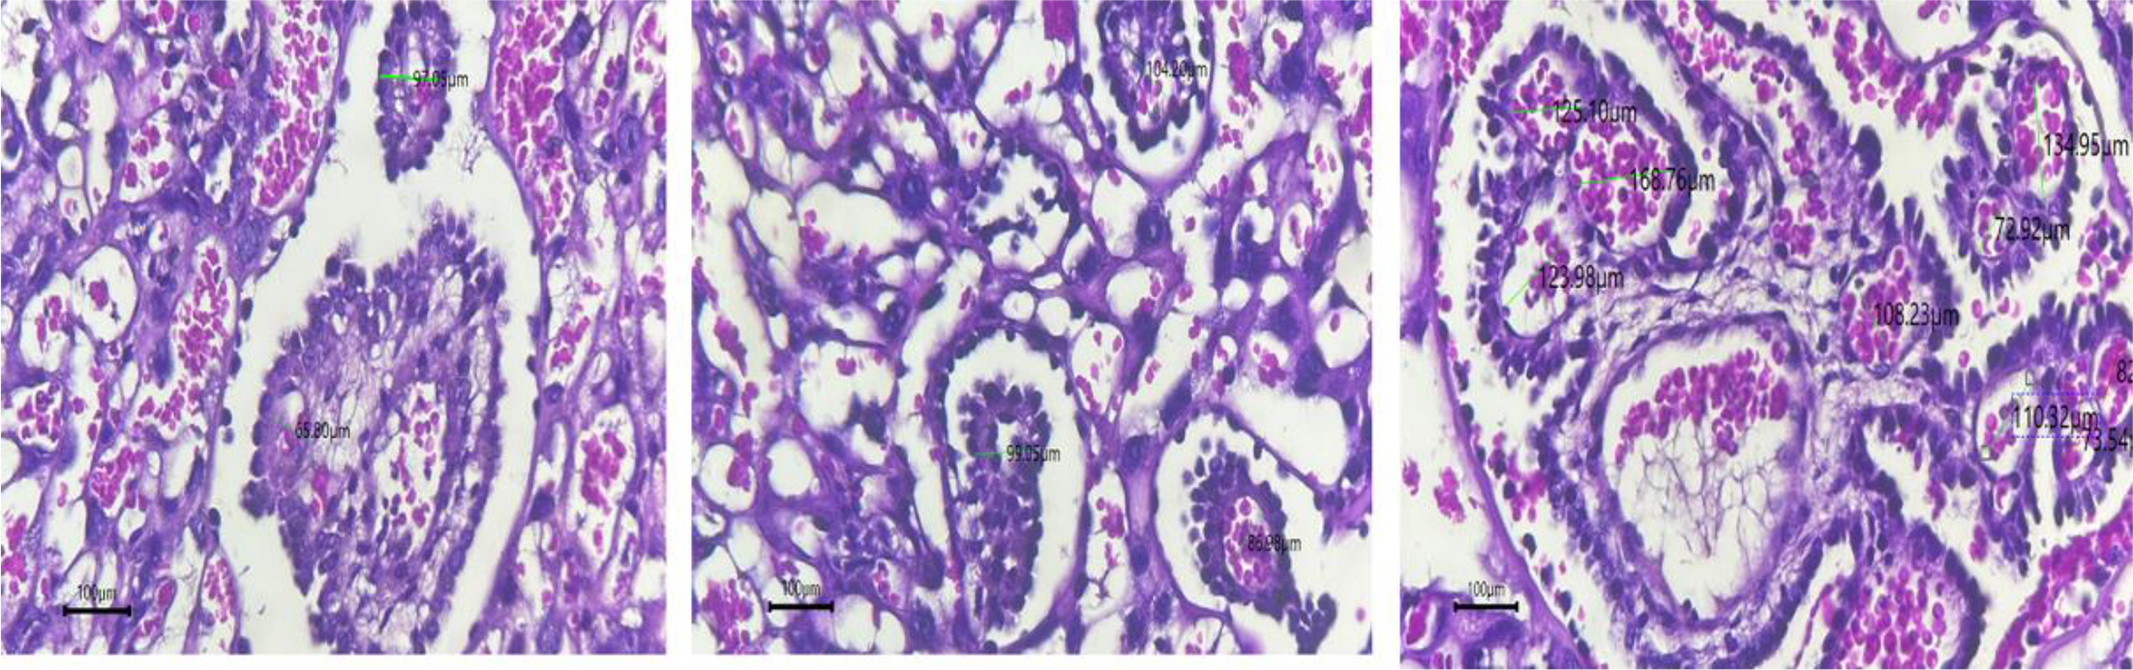

This image displays varying diameters of placental terminal villi, critical for gas and nutrient exchange. Terminal villi, resembling small fingers, consist of loose connective tissue and are covered by syncytiotrophoblasts, with visible blood capillaries enhancing exchange efficiency. Measurements of villous diameter ranged from 65.80 µm to 168.76 µm, reflecting the level of villous maturation and metabolic activity (Fig. 3).

Fig. 3. Histology of terminal villi diameter.

The larger diameters correlate with increased metabolic activity, facilitating optimal gas and nutrient transfer. The presence of prominent blood capillaries near the syncytiotrophoblast layer indicates effective circulatory activity, which is essential for supporting fetal growth. No pathological features, such as fibrosis or vascular insufficiency, were observed, suggesting normal placental function.